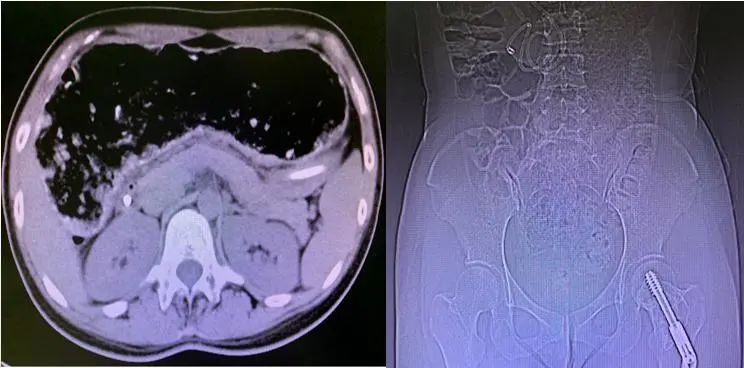

患者入院前肠腔大便蓄积及肠管显著扩张

术前肠道微生态预处理

经历一疗程肠道微生态治疗后,小李可耐受全量肠内营养,营养状况显著改善,但由于长期便秘,肠管仍有较大程度扩张。考虑到患者长期生活质量,同时患者经过一疗程肠道微生态治疗后,身体体质明显改善,手术耐受性可,考虑患者年轻且尚未生育,李宁教授为患者制定根治性手术方案,于2020-4-28在全麻下行腹腔镜下全结肠切除术+回肠直肠吻合术,作为中国医促会加速康复外科分会主任委员单位,科室加速康复外科护理小组按ERAS理念制定了康复方案,患者术后第二天开始排气排便,第三天开始排便,患者因长期便秘导致胃肠排空障碍,我们通过鼻饲管给予短肽型肠内营养支持治疗,并逐渐恢复口服进食,患者于术后1周顺利出院。